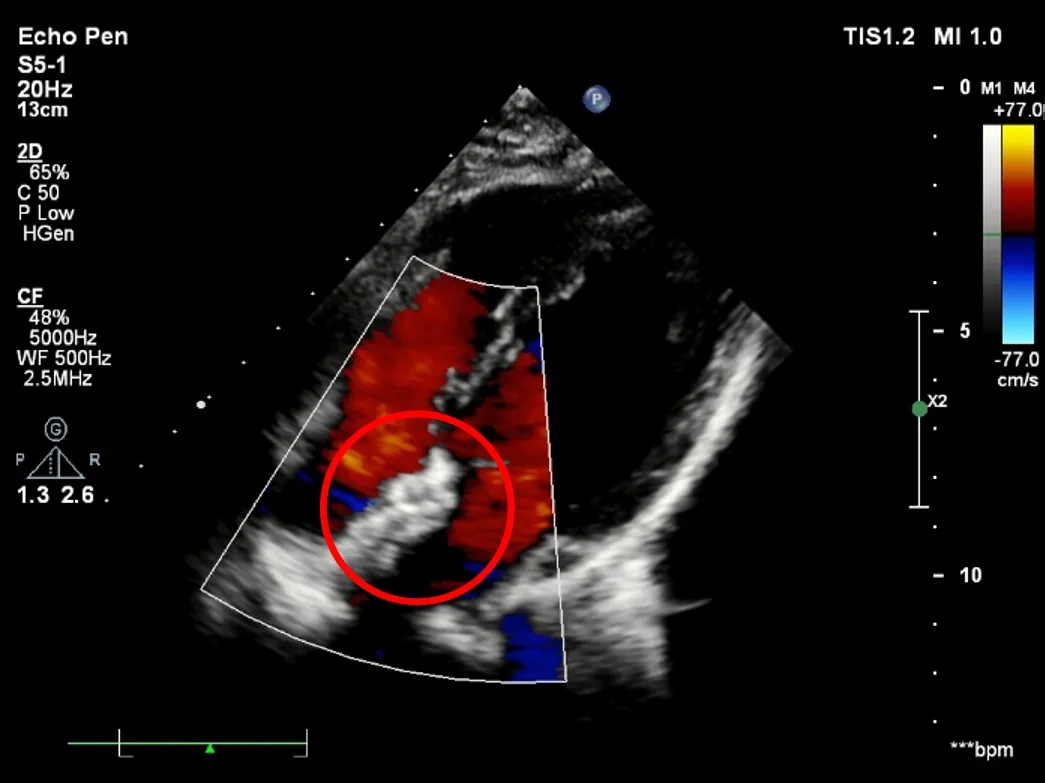

释放后超声

超声下可见室水平和房水平都无残余分流